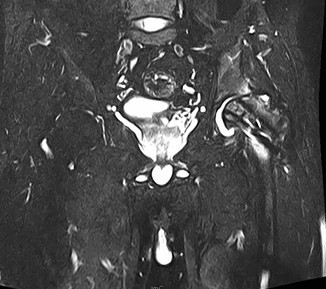

查体:左髋外侧可见一约25cm手术瘢痕,其上可见一点状结痂,左腿较右腿短缩,左腿肌肉较右腿萎缩,步态异常。左髋部无压痛,左腿外侧感觉异常,以左膝外侧为重,左髋外侧叩击痛,左足背动脉搏动未扪及异常。左下肢较右下肢短缩约2cm,左髋关节活动受限,其余各关节未见明显异常。 辅查:MRI示左股骨头坏死

诊断:左股骨头股骨颈粉碎性骨折切开复位内固定术后坏死 治疗:择期行关节置换术

股骨头坏死是一个病理演变过程,初始发生在股骨头的负重区,应力作用下坏死骨骨小梁结构发生损伤即显微骨折以及随后针对损伤骨组织的修复过程。造成骨坏死的原因不消除,修复不完善,损伤-修复的过程继续,导致股骨头结构改变、股骨头塌陷、变形,关节炎症,功能障碍。